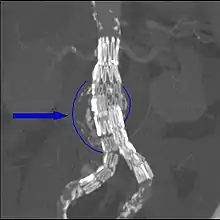

Sagittal CT image of an AAA Biomechanical AAA rupture risk prediction

Biomechanical AAA rupture risk prediction An axial contrast-enhanced CT scan demonstrating an abdominal aortic aneurysm of 4.8 by 3.8 cm